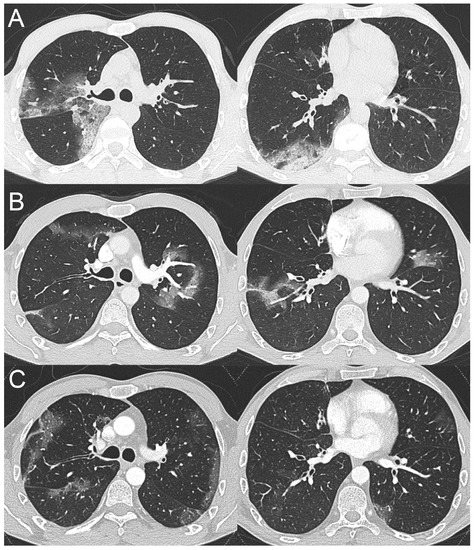

2.2. Case 2